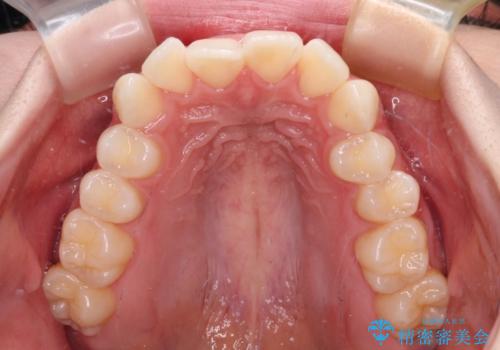

前歯のデコボコと深い咬み合わせ インビザラインできれいに改善

- 前歯のデコボコと下の前歯が隠れてしまう咬み合わせを気にして来院された患者様です。

インビザラインによる上下歯列の拡大と、IPR(歯と歯の間を削る)にるスペースの獲得により、口元のデコボコとディープバイトを改善することとしました。